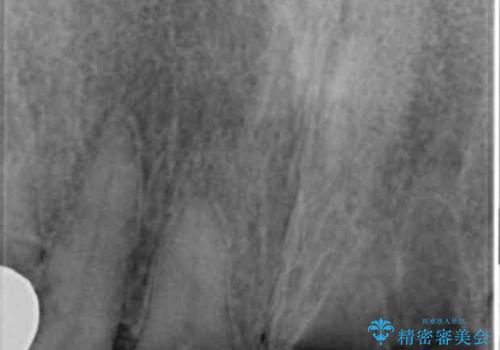

- 交通事故により前歯が折れたことを主訴に来院された患者様です。

精査したところ、前歯以外にも歯が折れており、上の歯の多くが保存不可能な状態でした。

保存可能な2本の歯を用いて、マグネットデンチャー(磁性アタッチメントを用いた入れ歯)による治療を行いました。